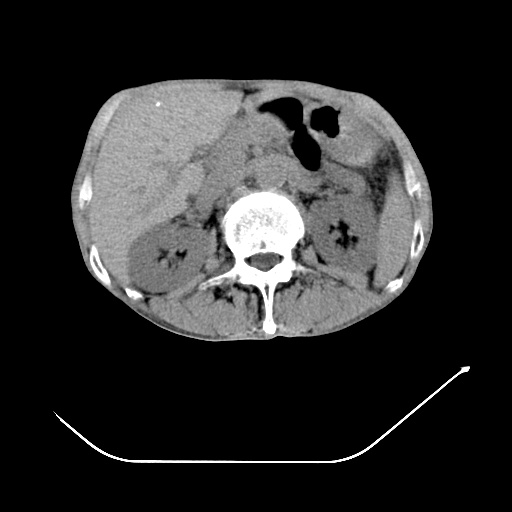

以下是引用zsl6918在2008-8-25 21:55:00的发言:[br]符合右肺周围性肺癌并肺内转移,左肺结核球。双肺肺气肿。腰椎附件转移。

以下是引用随光逐影在2008-8-25 22:03:00的发言:[br]1)考虑右肺下叶周围性肺癌并肺内转移,腰椎附件转移。2)左上肺结核(结核球形成)。3)双肺肺气肿(多发肺大泡形成)。4)双肺门区及纵隔内多发淋巴结钙化。